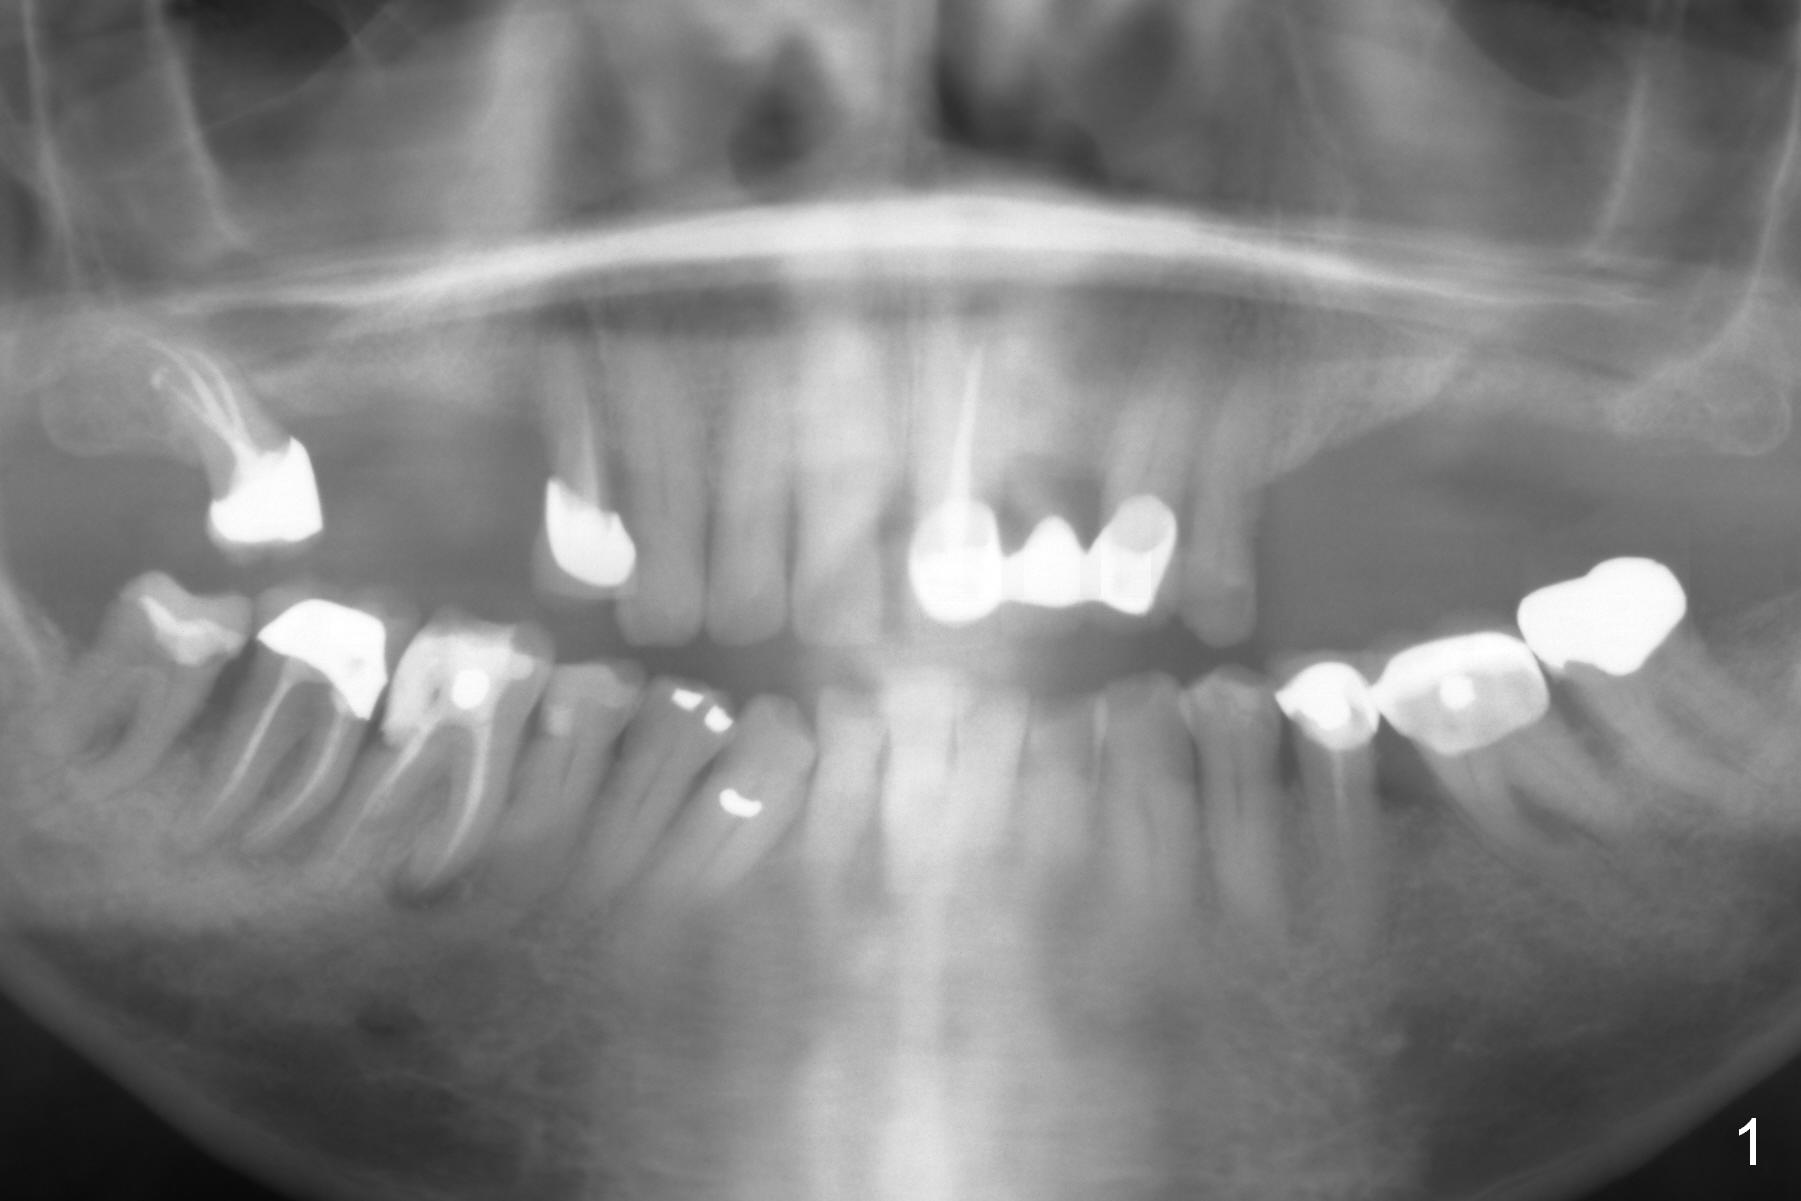

A 71-year-old man had poor dentition 4 years ago (Fig.1). Since then severe bone loss has occurred at the teeth #2 (Fig.2 *), 30 and 31 (Fig.3 *). An original plan is to place implants at #29 and 31 and fabricate a 3-unit bridge. Since the bone height at #31 is limited, primary stability may be questionable. It is advantageous to place 3 implants at #29-31. As the bone loss is severe and the sockets at #30 and 31 are long (Clindamycin), a fairly long portion of the implants at #30 and 31 will be not covered by the native bone (Fig.4 yellow line: 6-7 mm, bare) in spite of using 6 mm cuff (pink) of 7 mm abutments (brown). Use initial drill from DIO Sinus Master Kit with 5 mm stopper at #31 (green line), followed by insertion of a marked parallel pin. Use regular drills with stoppers of 10 and 8 mm at #29 and 30 (green line). Continue osteotomy at #31 with round drills (2.8 and 3.6 mm) with shorter stopper to avoid injury to the underlying Inferior Alveolar Canal (red dashed line). Pack allograft well around the implants at #30 and 31 before placing abutments to reduce periimplantitis and insert collagen plug around the abutments to prevent loss of the bone graft underneath. The last method to secure the bone graft is a retentive, splinted provisional.

It appears that the endo perio disease is more severe than 6 months ago (Fig.5,6). Prepare PRF and Extra Wide implants as well.